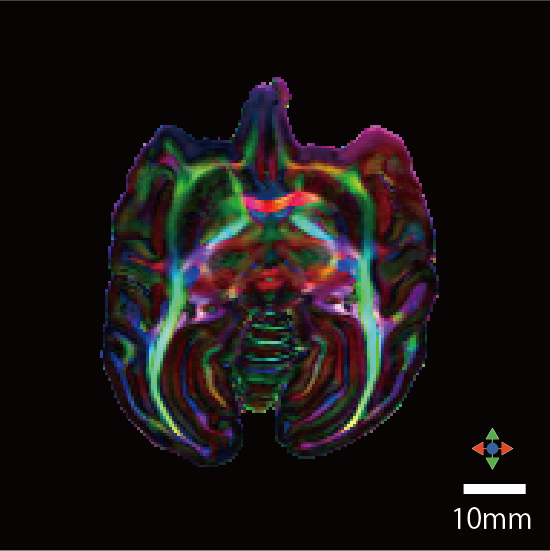

| カラーマップ |

![]() |